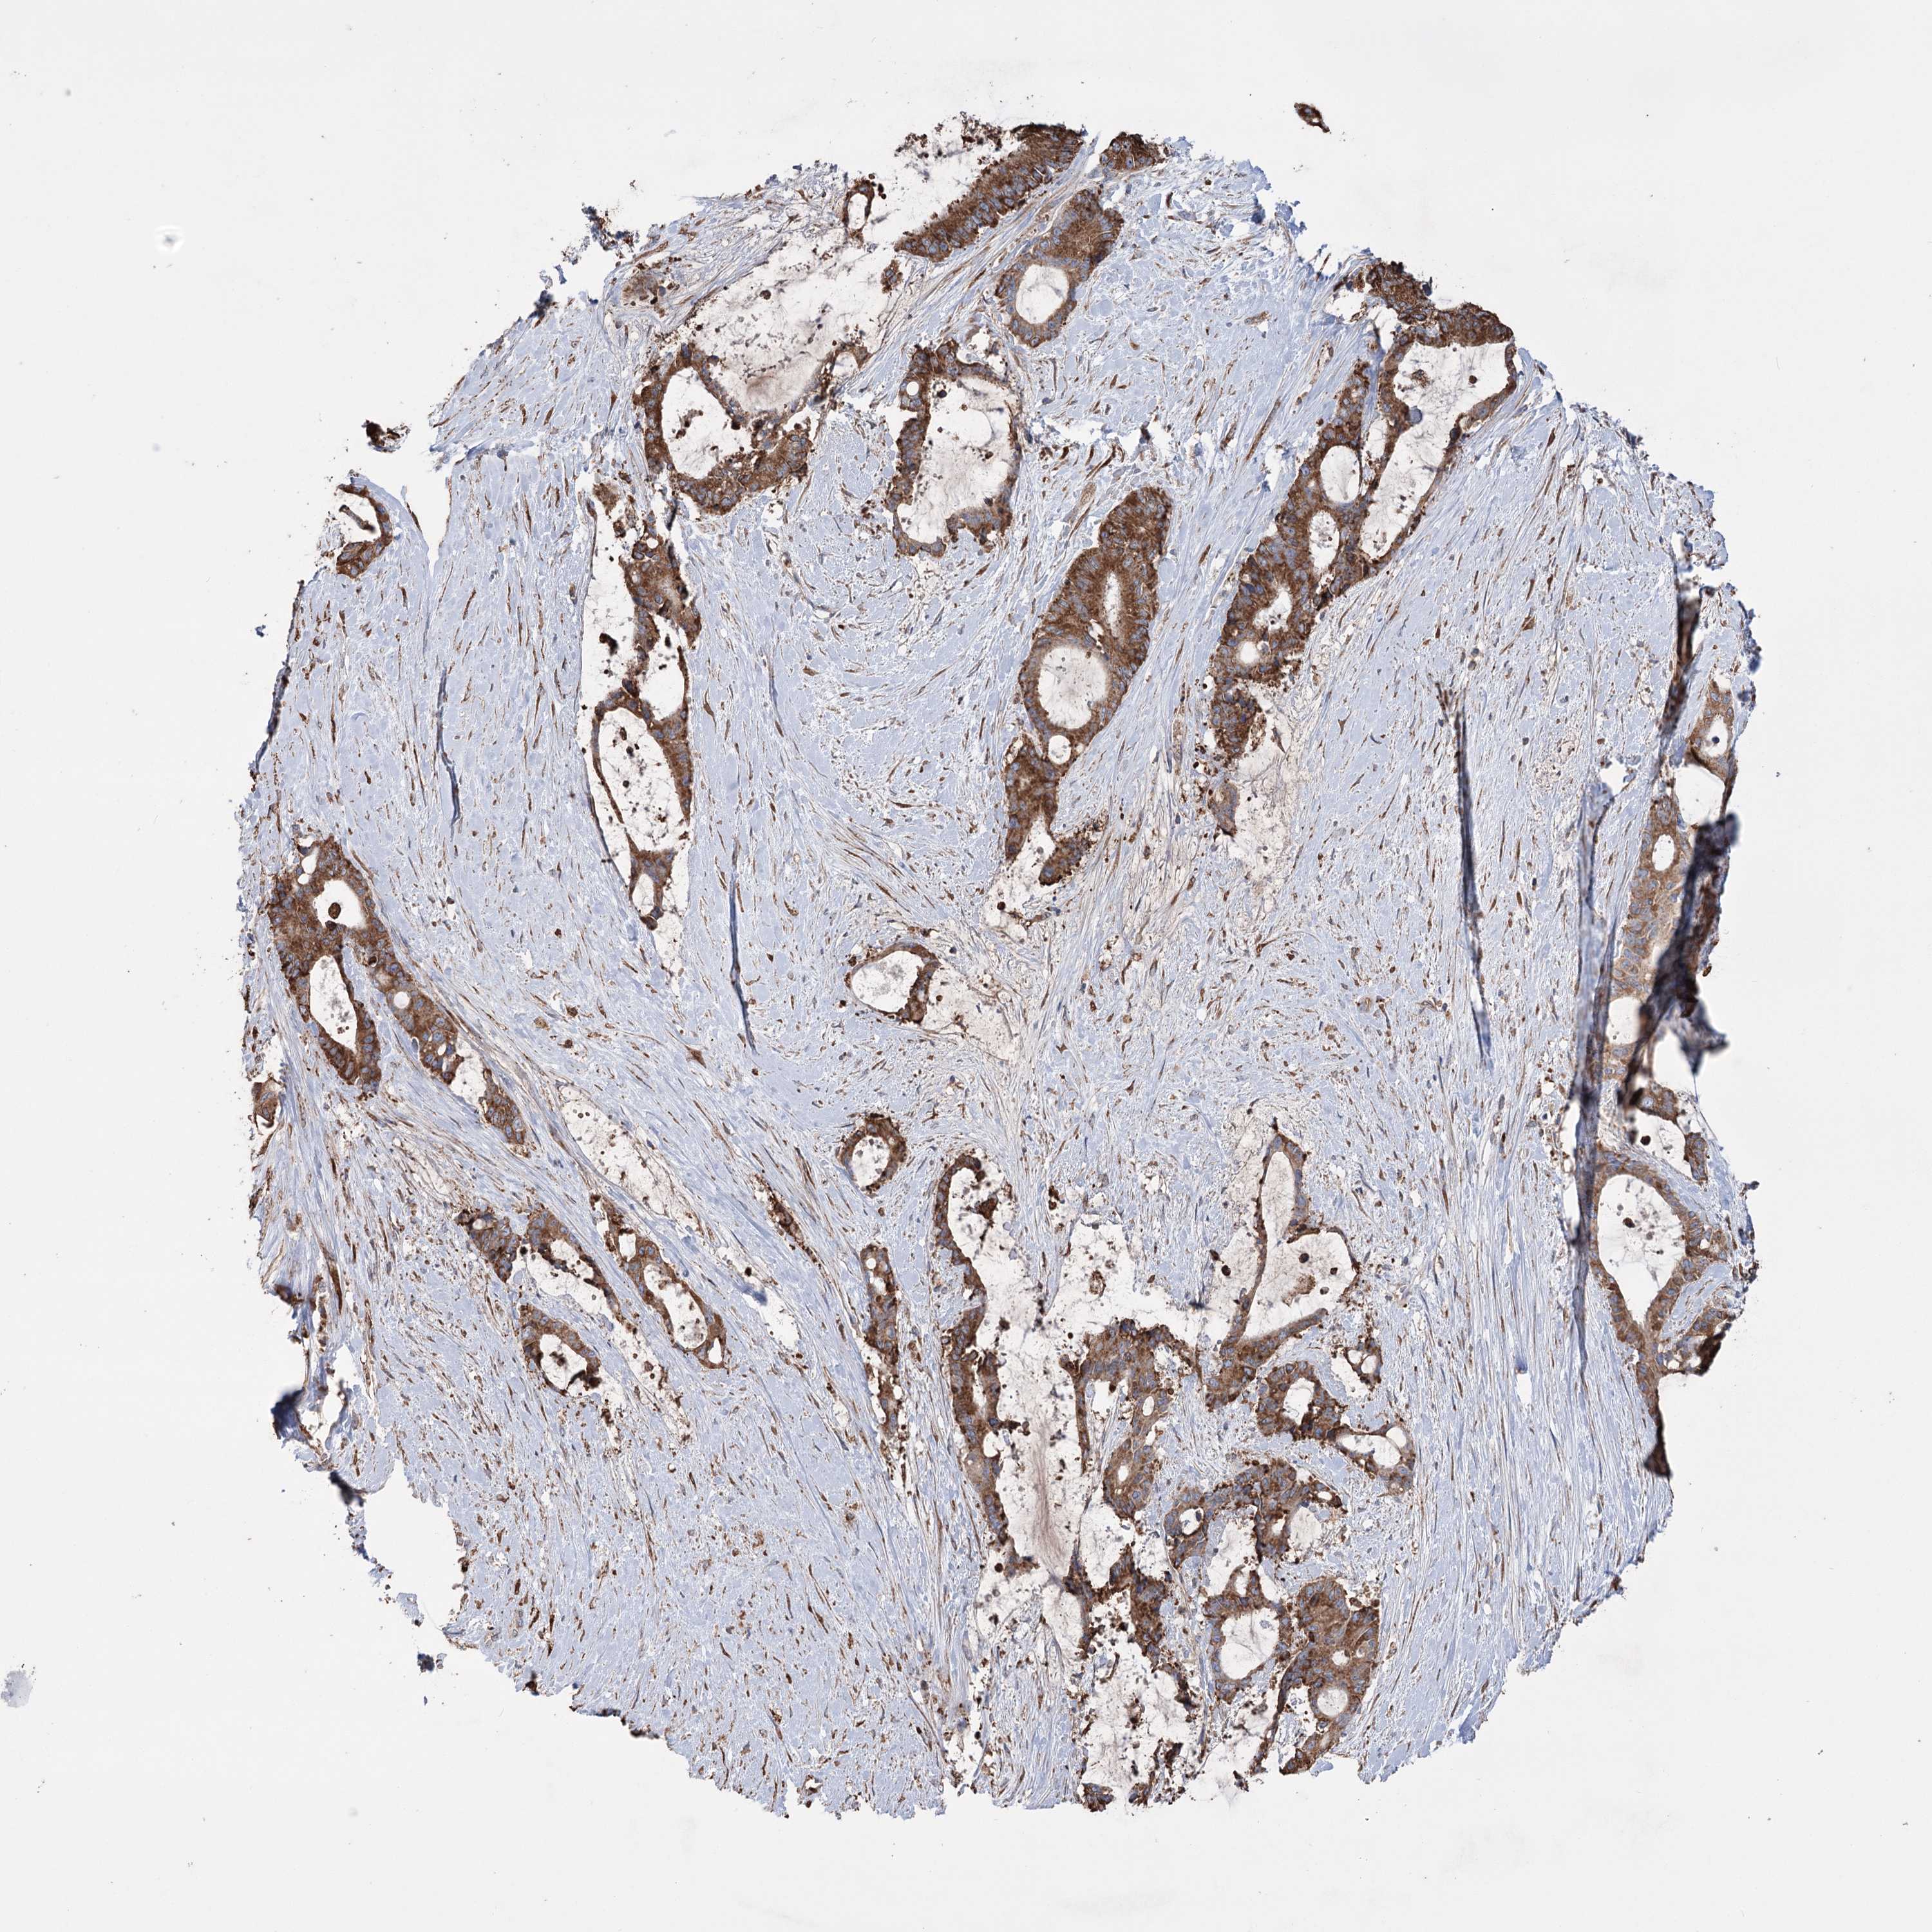

LIVER CANCER - Protein expressioni

A mouse-over function shows sample information and annotation data. Click on an image to view it in a full screen mode. Samples can be filtered based on level of antibody staining by selecting one or several of the following categories: high, medium, low and not detected. The assay and annotation is described here.

Note that samples used for immunohistochemistry by the Human Protein Atlas do not correspond to samples in the TCGA dataset.

Antibody stainingi

Antibody staining in the annotated cell types in the current human tissue is reported as not detected, low, medium, or high, based on conventional immunohistochemistry profiling in selected tissues. This score is based on the combination of the staining intensity and fraction of stained cells.

Each image is clickable and will lead to virtual microscopy that enables deeper exploration of all samples and also displays staining intensity scores, fraction scores and subcellular localization as well as patient and tissue information for each sample.

Antibody HPA038141

Antibody HPA038142

Staining

High

Medium

Low

Not detected

Intensity

Strong

Moderate

Weak

Negative

Quantity

>75%

75%-25%

<25%

None

Location

Nuclear

Cytoplasmic/membranous

Cytoplasmic/membranous,nuclear

Cholangiocarcinoma

Carcinoma, Hepatocellular, NOS